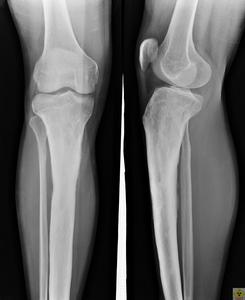

有條件者可行MRI及ECT檢查。X線片上可以看到多量骨密質增生,因X線片表現為大片濃白陰影,難以看出狹窄的骨髓腔與小透亮區。分層攝片與CT檢查可以探查出普通X線片難以辨出的小透亮區。根據病史、臨床表現和局部檢查,配合X線片即可確定診斷。骨髓炎X線片早期變化不明顯,晚期下頜支後前位片可見骨皮質不光滑,有小片死骨形成,或骨質增生。